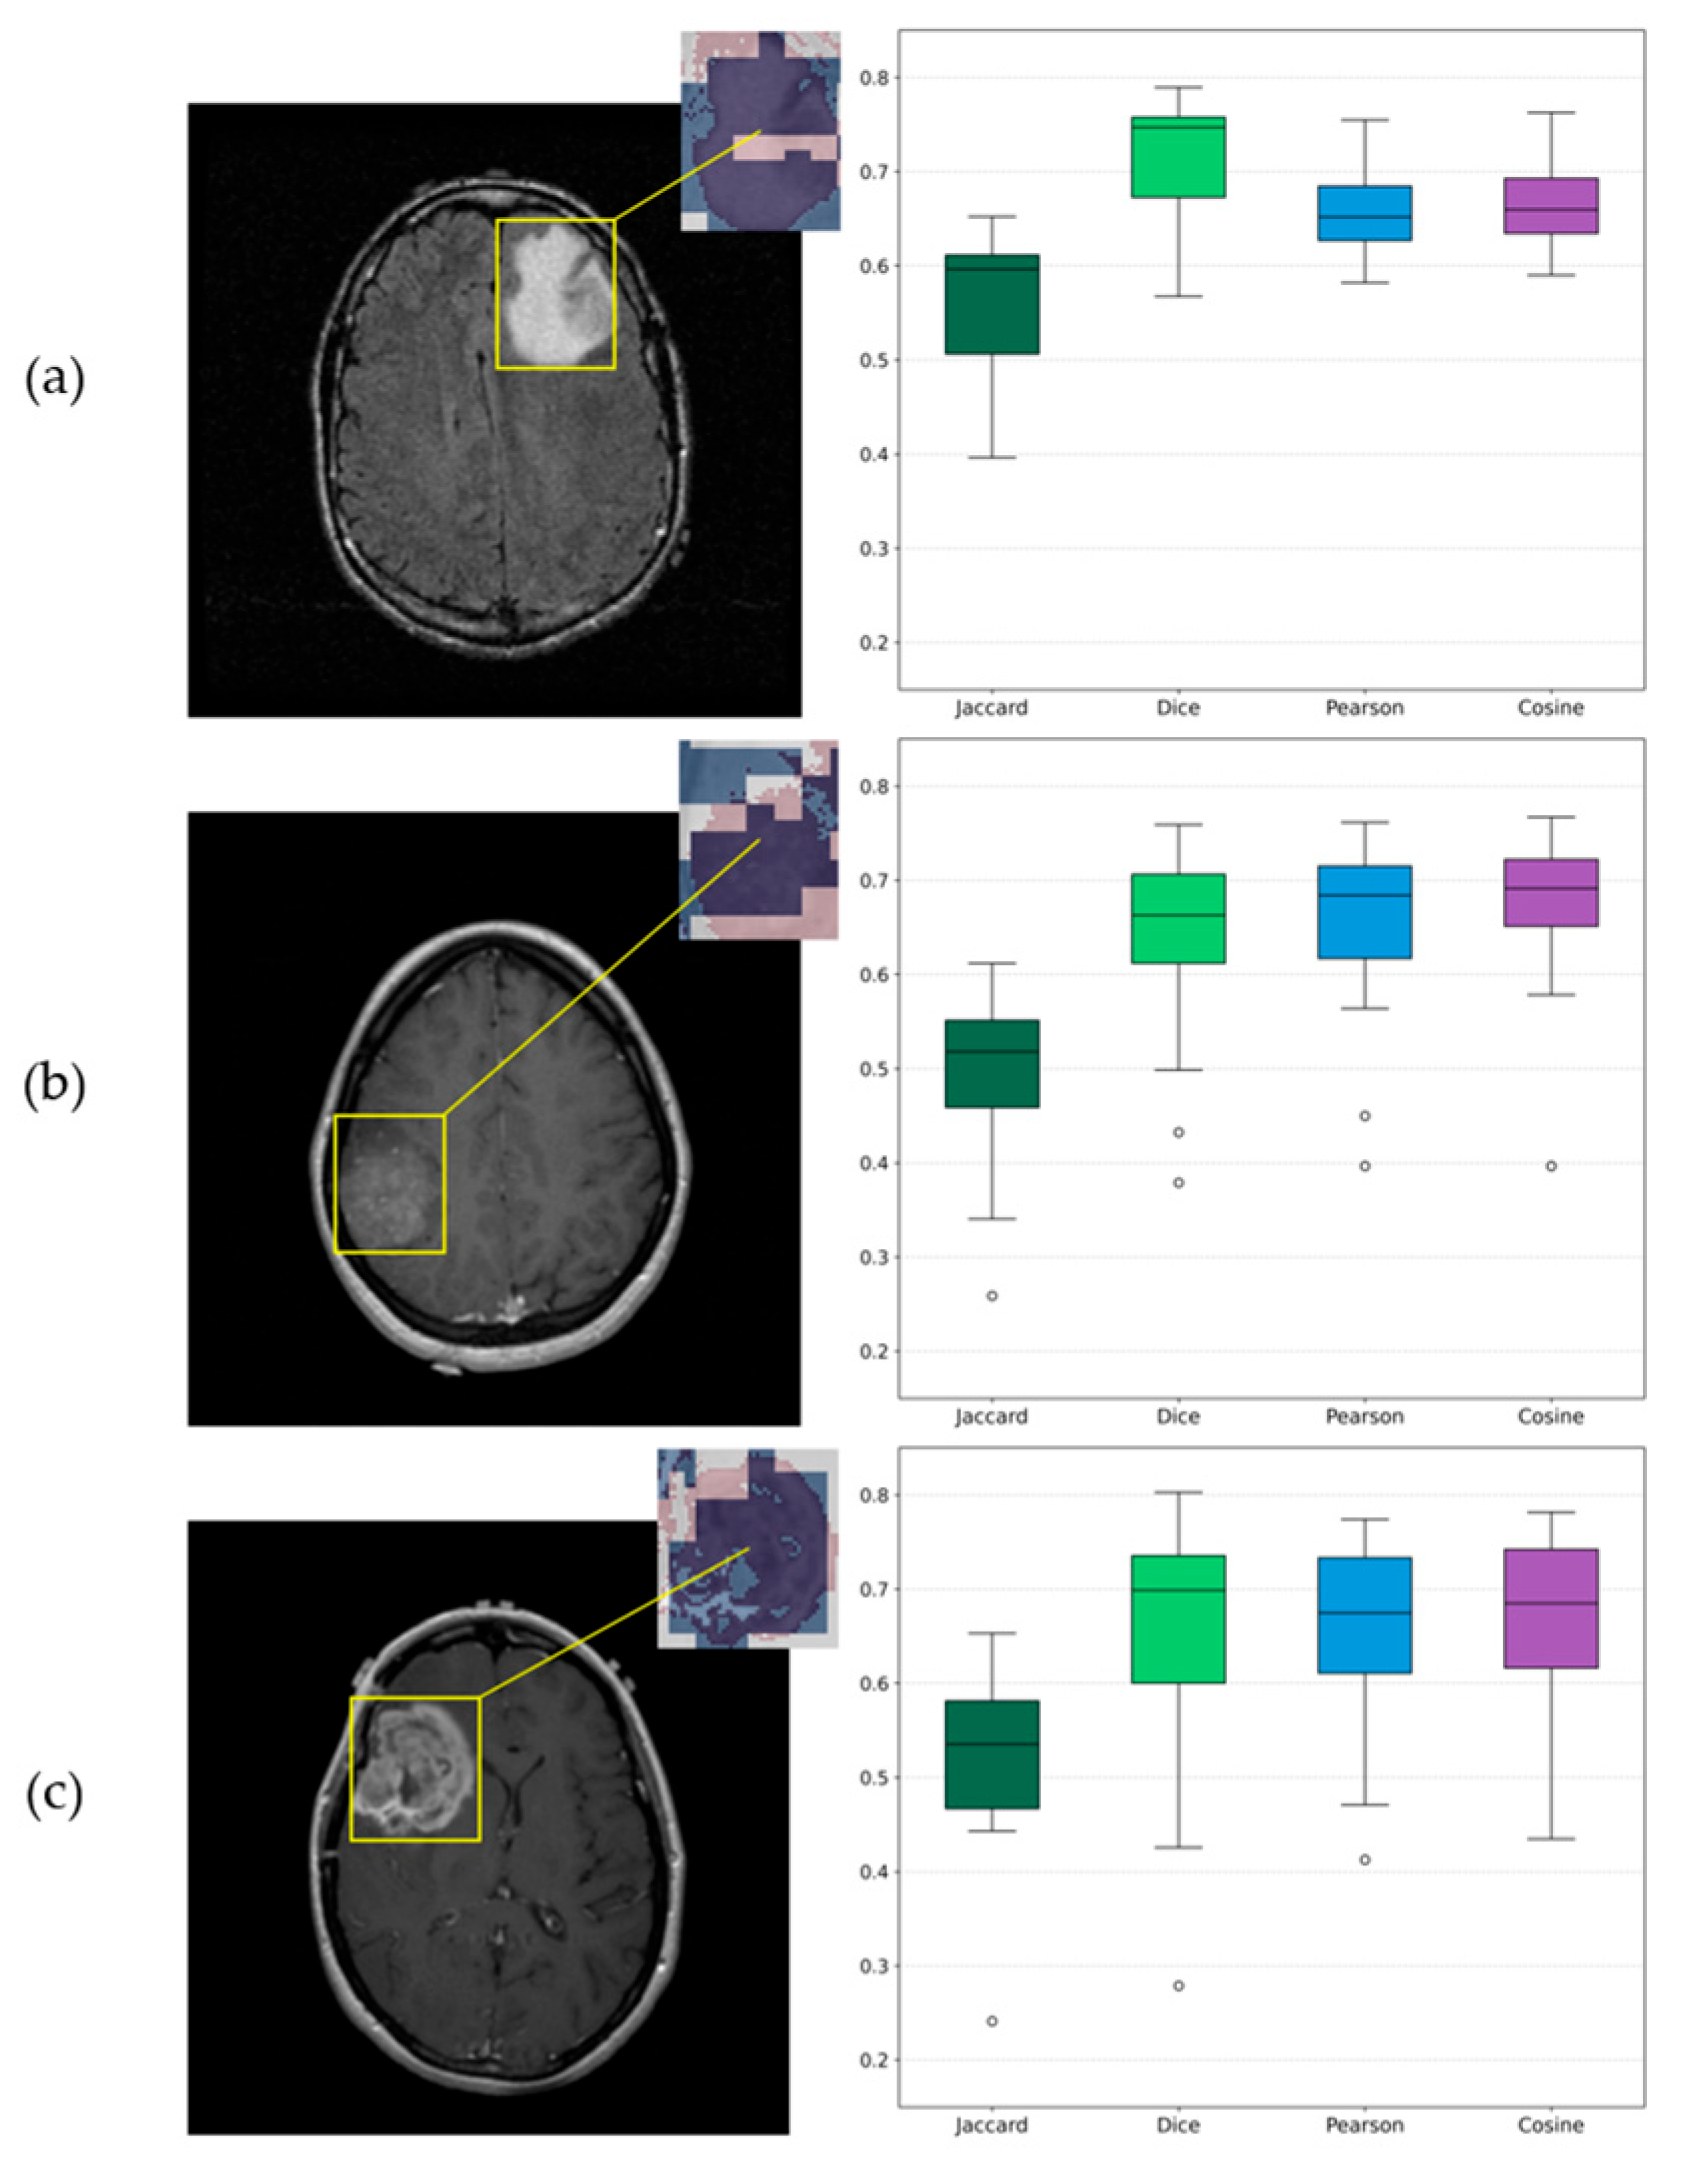

3.5. Explainable AI Insights

| Sample | Jaccard | Dice | Pearson | Cosine |

|---|---|---|---|---|

| Grade 2 | 0.56 ± 0.08 [0.51–0.61] | 0.72 ± 0.07 [0.68–0.76] | 0.66 ± 0.05 [0.63–0.69] | 0.67 ± 0.05 [0.64–0.70] |

| Grade 3 | 0.50 ± 0.10 [0.44–0.56] | 0.63 ± 0.11 [0.56–0.70] | 0.64 ± 0.11 [0.57–0.71] | 0.65 ± 0.12 [0.57–0.73] |

| Grade 4 | 0.51 ± 0.10 [0.45–0.57] | 0.64 ± 0.14 [0.55–0.73] | 0.65 ± 0.10 [0.59–0.71] | 0.66 ± 0.11 [0.59–0.73] |